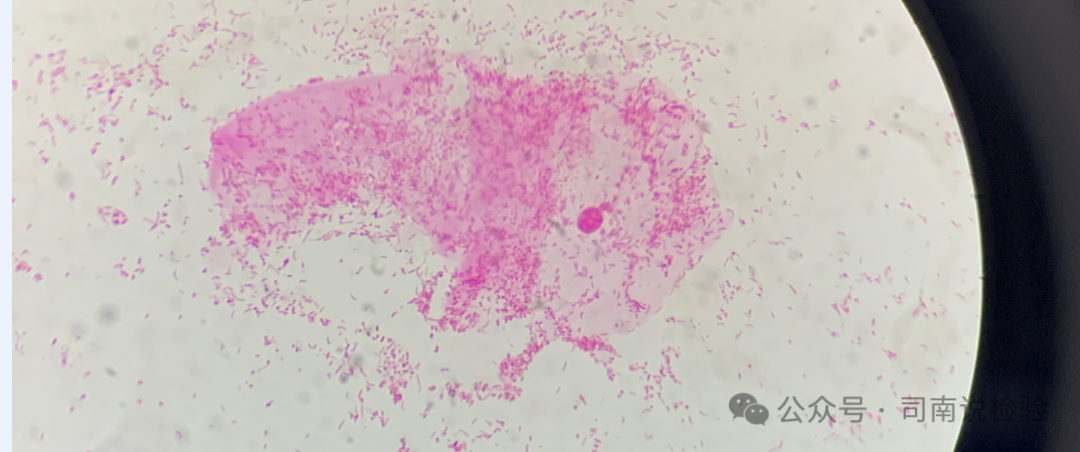

★BV的诊断目前主要根据Amsel临床诊断标准及革兰染色诊断标准。本实验室使用的是Nugent评分诊断标准,Nugent评分4~6 分为BV 中间态,≥7分诊断为BV。

★不是所有的加德纳菌都会产生唾液酸苷酶,也就是说不是所有的加德纳菌感染的患者唾液酸苷酶都会表现出阳性结果,因此在临床实践工作中需要注意干化学要与显微镜检查相配合(或者唾液酸苷酶与脯氨酸氨基肽酶相配合),以显微镜下看到的菌群为主要判断及作为报告回报的依据(细菌性阴道病诊治指南2021修订版的意见上指出,革兰染色Nugent评分标准才是BV诊断的实验室“金标准”)。

★其次即使是加德纳菌也不是所有的都能产生唾液酸苷酶,不产唾液酸苷酶的加德纳菌有可能处于相对较低的活性状态,对阴道微生态影响较小,在形态上,不产唾液酸苷酶的加德纳菌没有特别的辨识度。这些不产生唾液酸苷酶的加德纳菌就不会引起唾液酸苷酶的阳性反应。